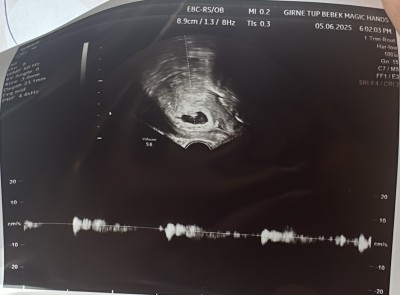

Kızlar kesemin şekli bozuk mu yoksa normal mi

Salı günü kesen bozuldu bebeğin kalp atışı yavaşladı dedi ben perşembe baska doktora gittim kesem daha toparlamış bebegin kalp atışı 100 dü kesemin şekli bozuk mu ve bu arada lekem geliyo yat hiç kalkma dedi

6+4